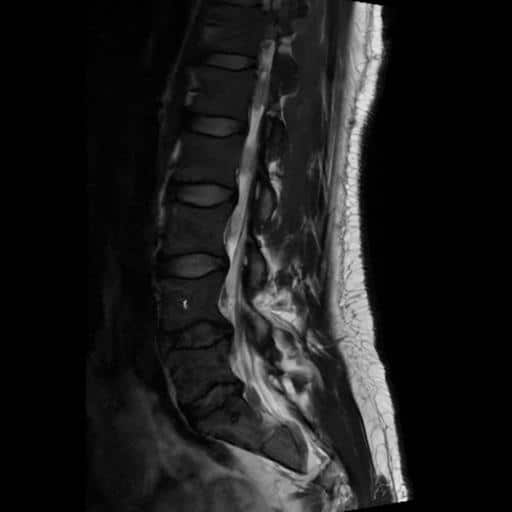

I got an MRI from a radiology clinic and confirmed that there was compression at the S1 nerve root. This at least ruled out more serious complications, but it also showed that we could really target that for recovery.

The injection was quick and easy. Just a couple of small pricks. First, the local anaesthetic, and then the injection. The radiologist looked at the imaging, and along with my symptoms, confirmed everything was consistent with an S1 nerve root inflammation. So that’s what he targeted.